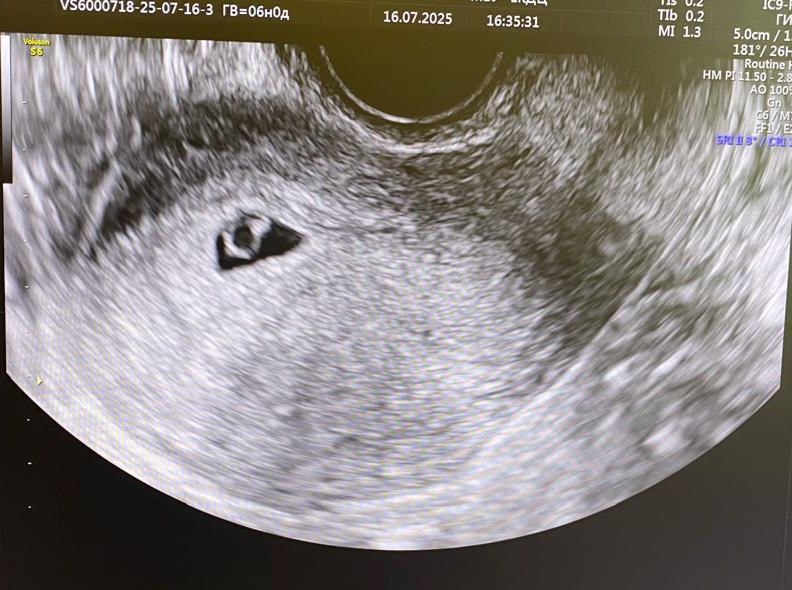

Первое узи 💗

УЗИ, КТГ, доплерсходила наконец - то на узи)) увидели бриллиантовое колечко 🔥

плодное яйцо: 12мм

ктр: 2,1 мм

сказали, что увидели только пульсацию,так как маленький еще 103уд в мин. (даже просили дыхание задержать)

шейка матки 36 мм

по мес у меня 6 недель а по Узи 5 и 5 недель))

у врача спросила сказала все соответствует, ну и конечно я еще у GPT чата спросила 😀 ттт растем хорошо